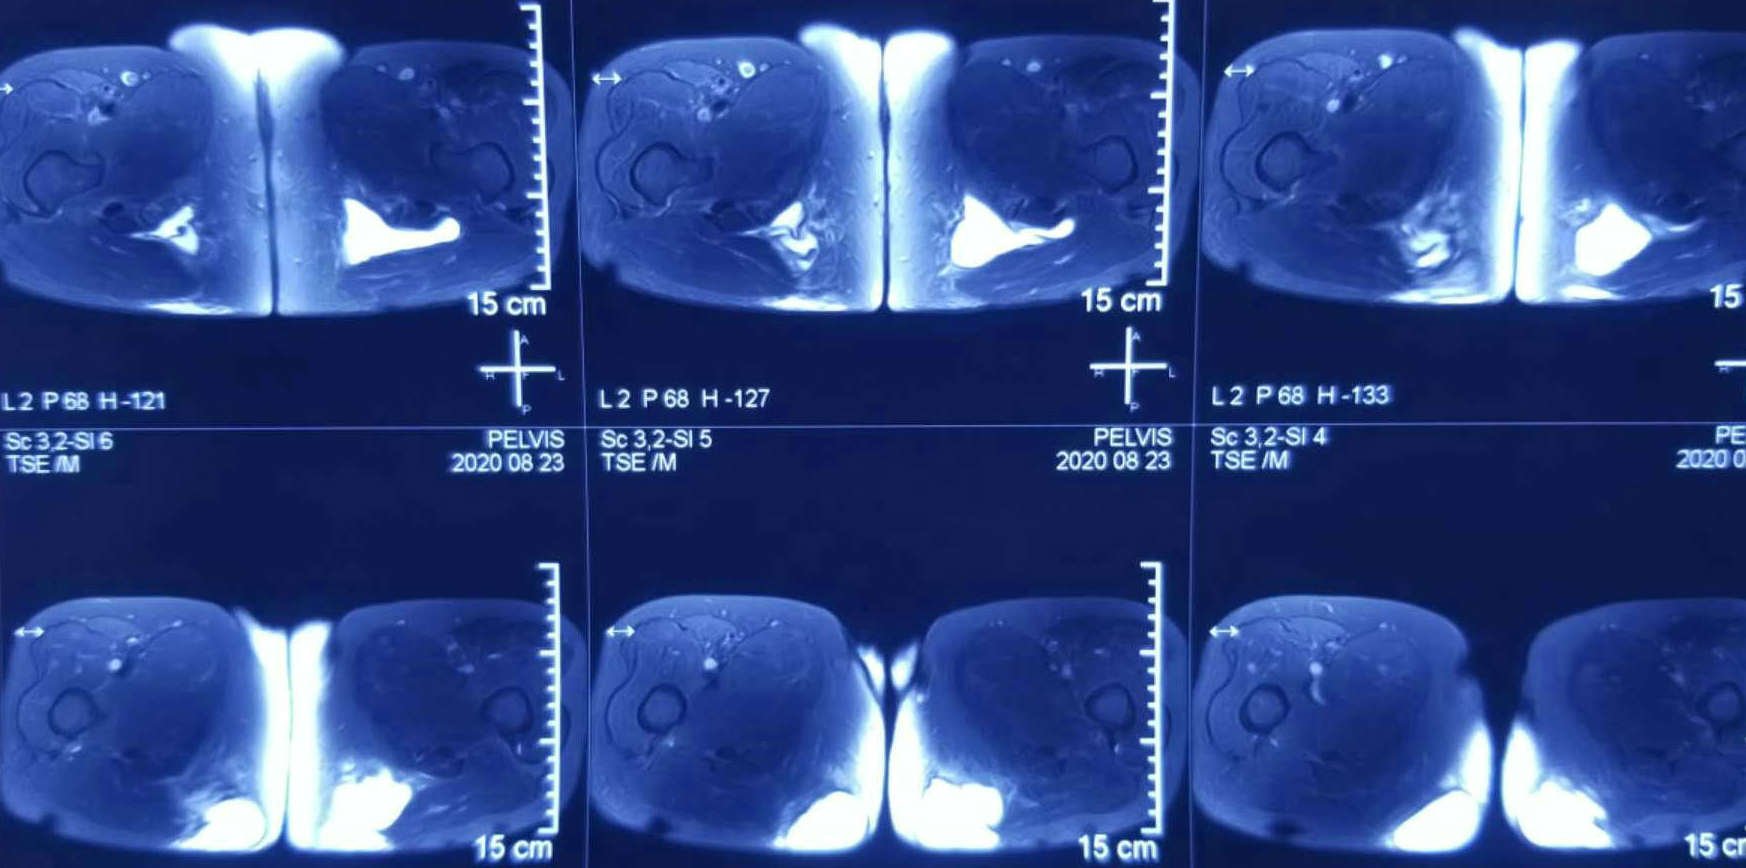

双髋横切面MRI

患者,女性,72岁,因进行性臀部包块增大伴坐位不适4月以恶性臀部肿瘤入院。近4月以来,发现双侧臀部包块,从鸡蛋大发展至较大肿块,伴坐位不适感和大便时不适感。患者有近30年类风湿性关节炎既往病史,近8年以来双膝疼痛加重、跛行并伴有严重内翻畸形,行走非常困难,主要以双手撑地,臀部着地方式移动身体,即“以臀代步”,日常生活以坐姿为主。入院后,我院继续完善相关检查,超声提示患者左、右臀部皮下分别探及约4.7×3.6,3.6×3.2cm大小的无回声包块,外形不规则,下缘向软组织深部延伸,边界尚清,内透声欠佳,其内可见细密点状漂浮,诊断意见为双侧臀部皮下囊性占位病变,经核磁及CT进一步诊断为囊性占位病变深及坐骨结节及肛门肌群旁,穿刺活检提示符合良性囊性病变。术前,确诊为双侧臀部皮下及深部巨大囊肿。

经我院医护人员充分准备后,由骨科三病区副主任王旭主刀,主治医生王亚鹏辅助,成功进行罕见双侧臀部巨大囊肿切除手术。术中可见囊性短期内体积进一步增大,左、右侧包块分别约6×4×3,5×4×3cm大小,均内含大量淡黄色囊液,有少量软骨样白色漂浮小粒,囊壁较厚,囊肿发自坐骨结节肌腱及其附着部,囊肿已经压迫肛门周围肌群,整个手术出血约200ml左右,历时3小时完成。